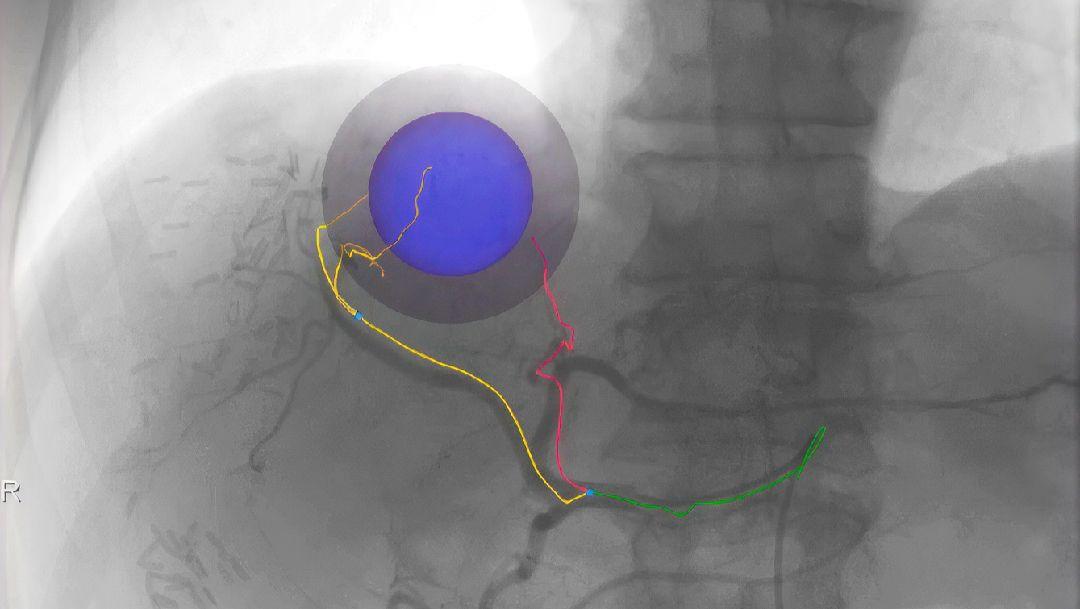

Imaging modalities for liver monitoring

Therapy options